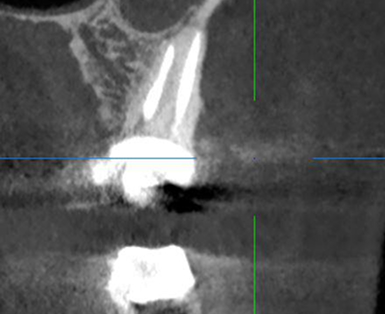

Сохранение зуба при наличии кисты, проростающей в гайморову пазуху

Проблема: У пациента боли в проекции гайморовой пазухи, заложенность носа, боли при пережевывании пищи.

Лечение: Проведено эндодонтическое перелечивание зуба под микроскопом: удалены ранее внесённые материалы, выполнена тщательная механическая и медикаментозная обработка корневых каналов с учётом их анатомии. Особое внимание уделено устранению инфекционного очага (кисты), связанного с воспалением в области гайморовой пазухи. После этого каналы герметично запломбированы, а коронковая часть зуба временно восстановлена для дальнейшего покрытия зуба коронкой.

Результат: После проведённого эндодонтического лечения болевые ощущения при жевании устранены, дискомфорт и давление в области гайморовой пазухи исчезли, восстановилось нормальное носовое дыхание. Зуб сохранён, его функция восстановлена. После фиксации коронки полностью восстановлены анатомическая форма и жевательная эффективность, нагрузка распределяется корректно.